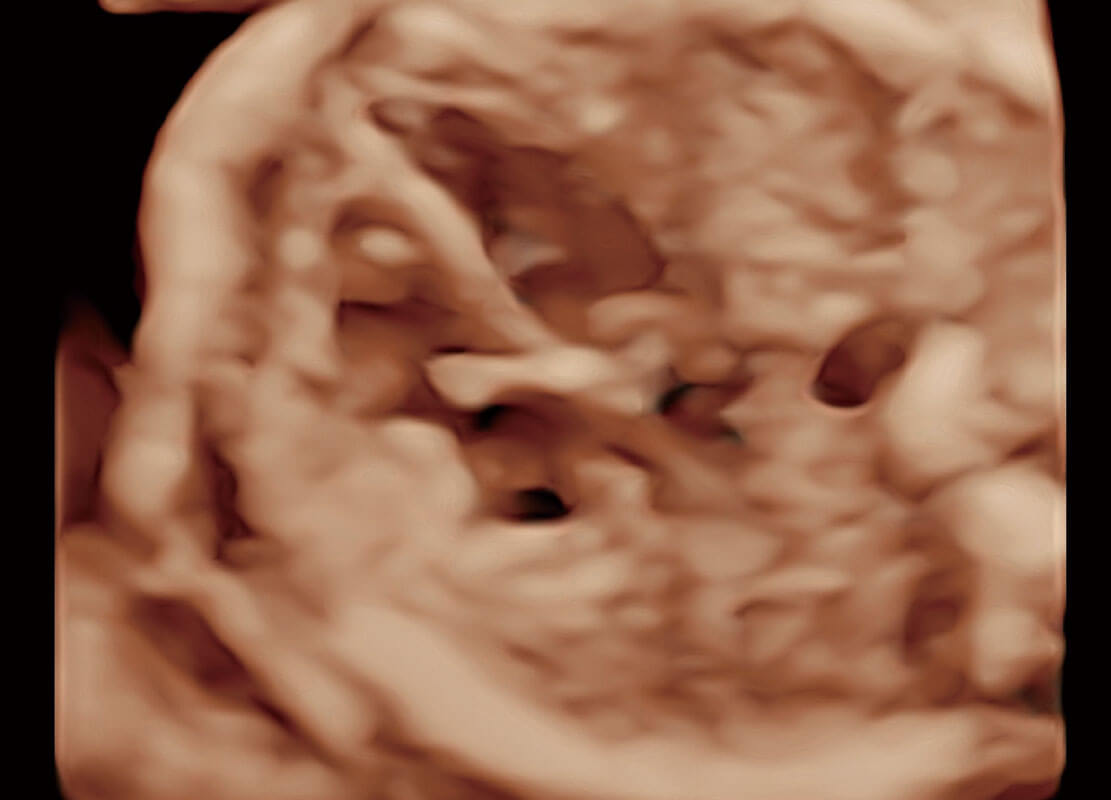

中晚孕筛查

P60提供简单易学易用的高端诊断工具,为您中晚孕筛查提供快速清晰的解剖信息。

S-Fetus能够助您在实时扫查过程中自动识别标准切面、自动测量并录入报告。一个按键,即可快速、高效地获取胎儿生理指标,简化您的产科检查操作。